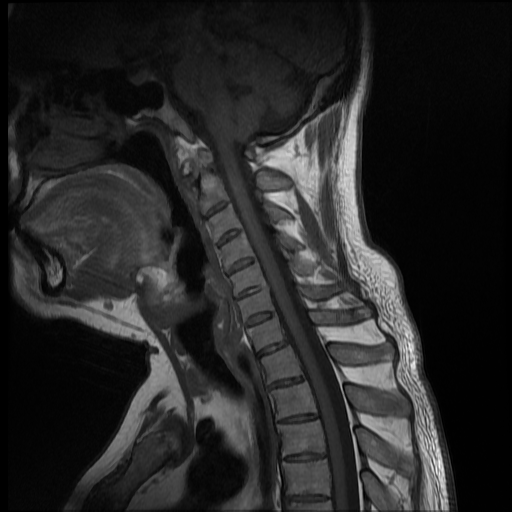

La espondilitis anquilosante (EA), es una enfermedad autoinmune inflamatoria crónica que afecta principalmente a las articulaciones de la columna vertebral y causa dolor crónico severo, afecta principalmente a las articulaciones de la columna, las articulaciones sacroilíacas y los tejidos blandos adyacentes, como los tendones y los ligamentos. En casos más avanzados, esta inflamación puede dar lugar a fibrosis y calcificación, dando como resultado la pérdida de flexibilidad y la fusión de la columna, asemejándose a un “bambú” con una posición inmóvil. Este caso se enfoca a paciente de 37 años de edad, que manifiesta rigidez y perdida de la linealidad de la columna cervical, encontrando a través del estudio de MRI calcificación de los ligamentos anterior y posterior de la columna cervical, más fusión de vértebras cervicales.

Ankylosing spondylitis (AS) is a chronic inflammatory autoimmune disease that primarily affects the joints of the spine and causes severe chronic pain. It primarily affects the joints of the spine, the sacroiliac joints, and adjacent soft tissues such as tendons. and the ligaments. In more advanced cases, this inflammation can lead to fibrosis and calcification, resulting in loss of flexibility and fusion of the spine, resembling a “bamboo” with an immobile position. This case focuses on a 37-year-old patient, who manifests rigidity and loss of linearity of the cervical spine, finding through the MRI study calcification of the anterior and posterior ligaments of the cervical spine, plus fusion of cervical vertebrae.

Paciente de 37 años de edad, no refiere trauma reciente, indica que hace mas o menos dos años inicio con dolor a nivel del cuello, y empezó a notar que el mismo se estaba inclinando hacia el lado izquierdo, esta inclinación ha ido en aumento y no le permite colocar el cuello de forma recta, causándole dolor e incomodidad. Acude a consulta y luego de ser evaluado por facultativo le solicitan estudio de resonancia magnética de columna cervical.

Se observa perdida de la lordosis normal de la columna cervical.

Se observa hipo intensidad del ligamento longitudinal anterior y posterior de la columna cervical, también se observa perdida de la movilidad y rigidez de la misma, los ligamentos interespinosos se ven hipointensos en T2 y en T1, al igual que el pliegue nucal, lo que sugiere calcificación de estas estructuras anatómicas.

Se observa fusión de las vertebras cervicales 5-6 y 6-7, dando la apariencia de bambú.

• Perdida de la lordosis

• Ligamentos espinales anterior, posterior, interespinosos y pliegue nucal calcificados

• Fusión de vertebras cervicales 5-6 y 6-7.